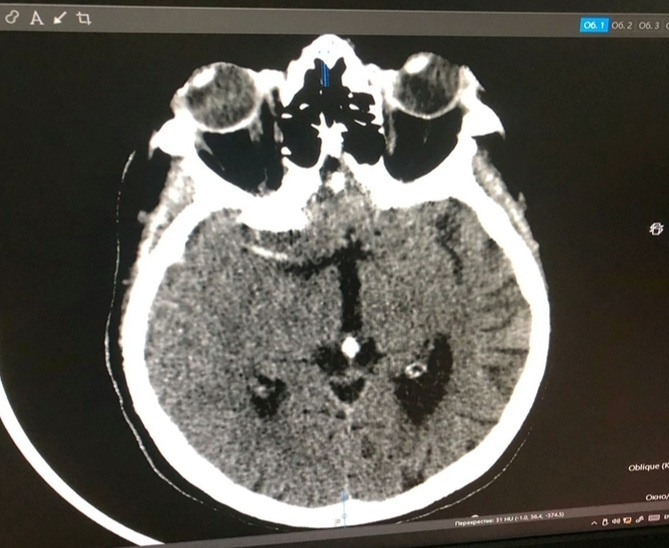

Пациентку доставили в приёмный покой ОКБ, ей провели РКТ головного мозга и исследование проходимости сосудов. Выяснилось, что соотношение поврежденного и не подлежащего восстановлению участка и жизнеспособной зоны мозга составило 1 к 4. Врачи приняли решение провести тромбоэкстракцию — высокотехнологичный метод удаления тромба.